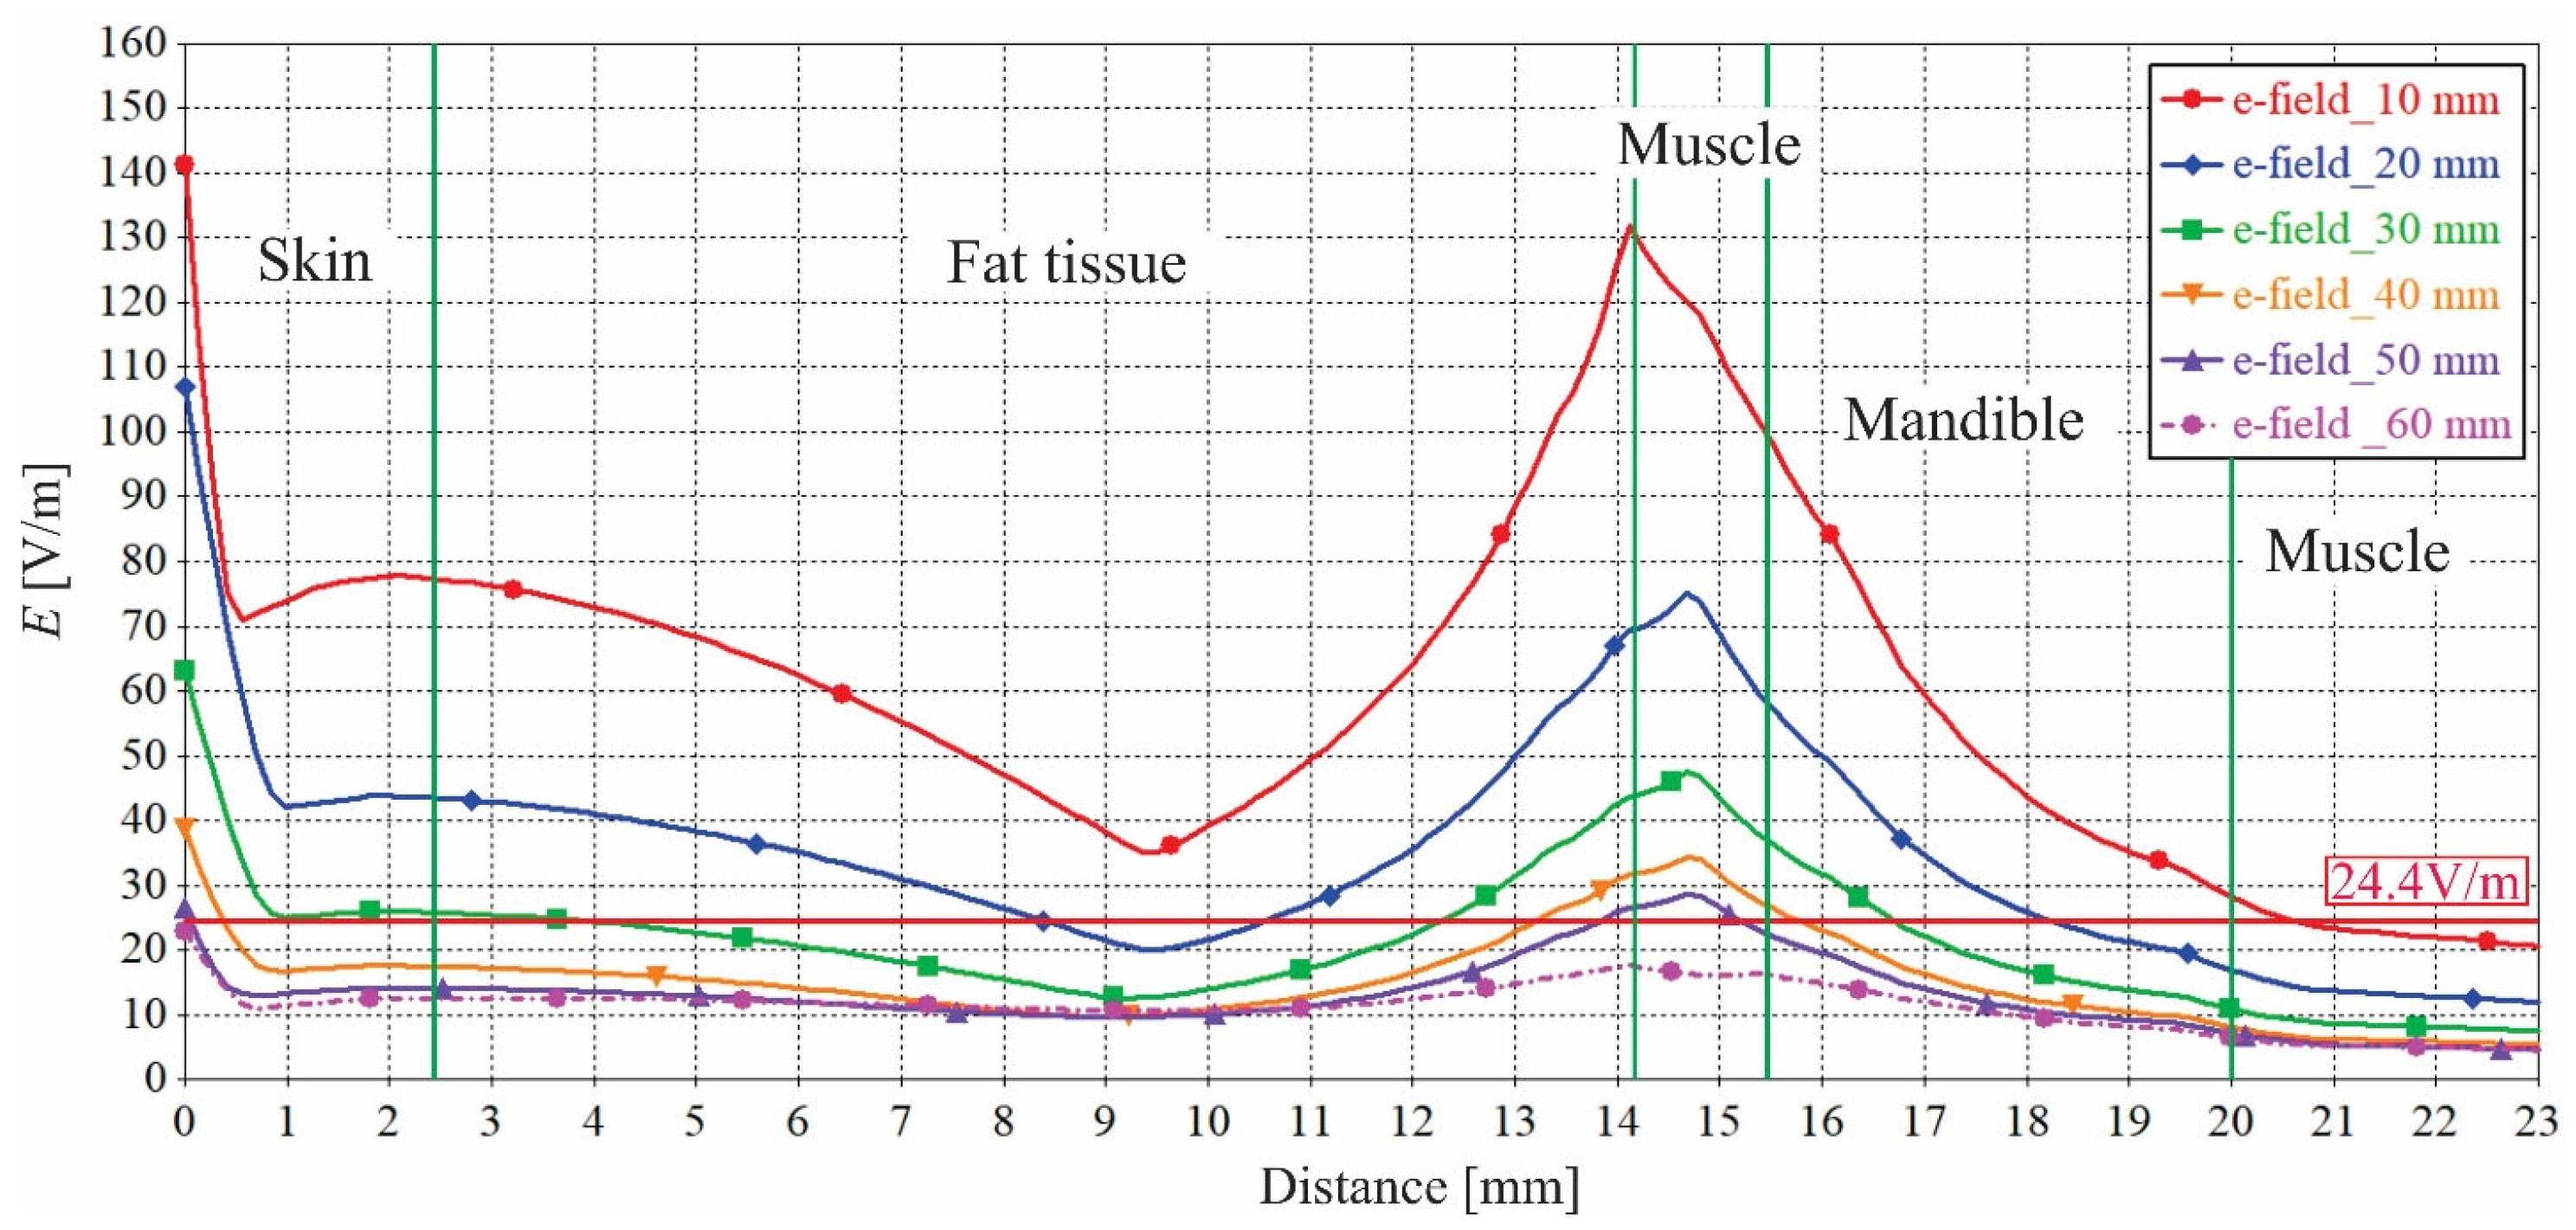

3.3. Impact of the Face-to-Phone Distances on the Electric Field and SAR Distribution in the Implant Vicinity